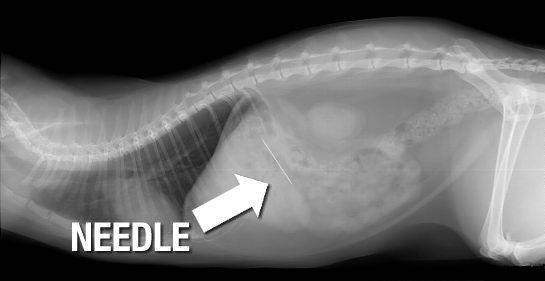

Якщо ви раптом шили, а потім забули, що у вас в роті інструмент і, сглотнув, чхнув, пирхнувши, розреготавшись, проковтнули голку, відразу ж викликайте швидку. Це однозначно. До того моменту, поки не приїхала швидка не можна:

Головне не лякайтеся і не робіть судомних рухів горлом. Цілком можливо, що голка просто застрягне в верхньому відділі стравоходу, як риб'яча кістка і приїхав лікар відразу витягне її на місці.

Голка цілком може проколоти стравохід, особливо якщо це гострий і вузький номер, і піти в сторону легкого або серця. Однак народні страшилки про блукання голок по тілу людини зазвичай не більше, ніж байки. Голка частіше залишається в м'язових тканинах, врости в них, де може залишитися навіть на все життя, часом не викликаючи розладів. Це в разі, якщо процес не супроводжується запаленням. Найгостріша голка, що залишилася в тканинах, буде пересуватися до пори до часу, на найнікчемніше відстань. Зазвичай серйозно переміститися голки можуть тільки по вені або потрапили у велику порожнину, наприклад, черевну. Найчастіше, це прерогатива ін'єкційних голок.

Найбільш ймовірно, що голка застрягне в звуженому ділянці стравоходу і викликатиме больові відчуття. Тоді вас відвезуть в лікарню, зроблять рентген і визначать її місцезнаходження. Часто буває, що голка проходить до шлунка і є така ймовірність, що вона може вийти з каловими масами через кишечник, але ризикувати, все-таки, не варто. Стійка затримка голки в шлунку або в кишечнику може призвести до дуже тяжких наслідків. Голка може проколоти стінку шлунка або кишки, що небезпечно зараженням і перитонітом. Тому при ковтанні голок необхідно негайно викликати швидку.